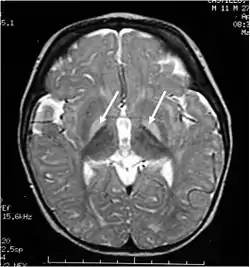

![]() МРТ голови. Гіперінтенсивний сигнал від пошкоджених базальних ядер в T2-режимі. МРТ голови. Гіперінтенсивний сигнал від пошкоджених базальних ядер в T2-режимі. | |

Некон'югований білірубін дуже добре розчиняється в жирах, але майже не розчиняється в воді. Тому для транспортування до клітин печінки він зв'язується з альбуміном. При значному підвищенні рівня білірубіну, коли транспортна ємність альбуміну вичерпана, вільний білірубін може подолати гемато-енцефалічний бар'єр і проникнути в головний мозок до базальних гангліїв. Там білірубін викликає гальмування процесів окисного фосфорилювання, що призводить до загибелі клітин. Базальні ганглії (бліда куля, лушпина і хвостате ядро) дуже чутливі до дії білірубіну і пошкоджуються найбільше, тому й закріпилося назва патології «ядерна жовтяниця». Важка енцефалопатія призводить до смерті.